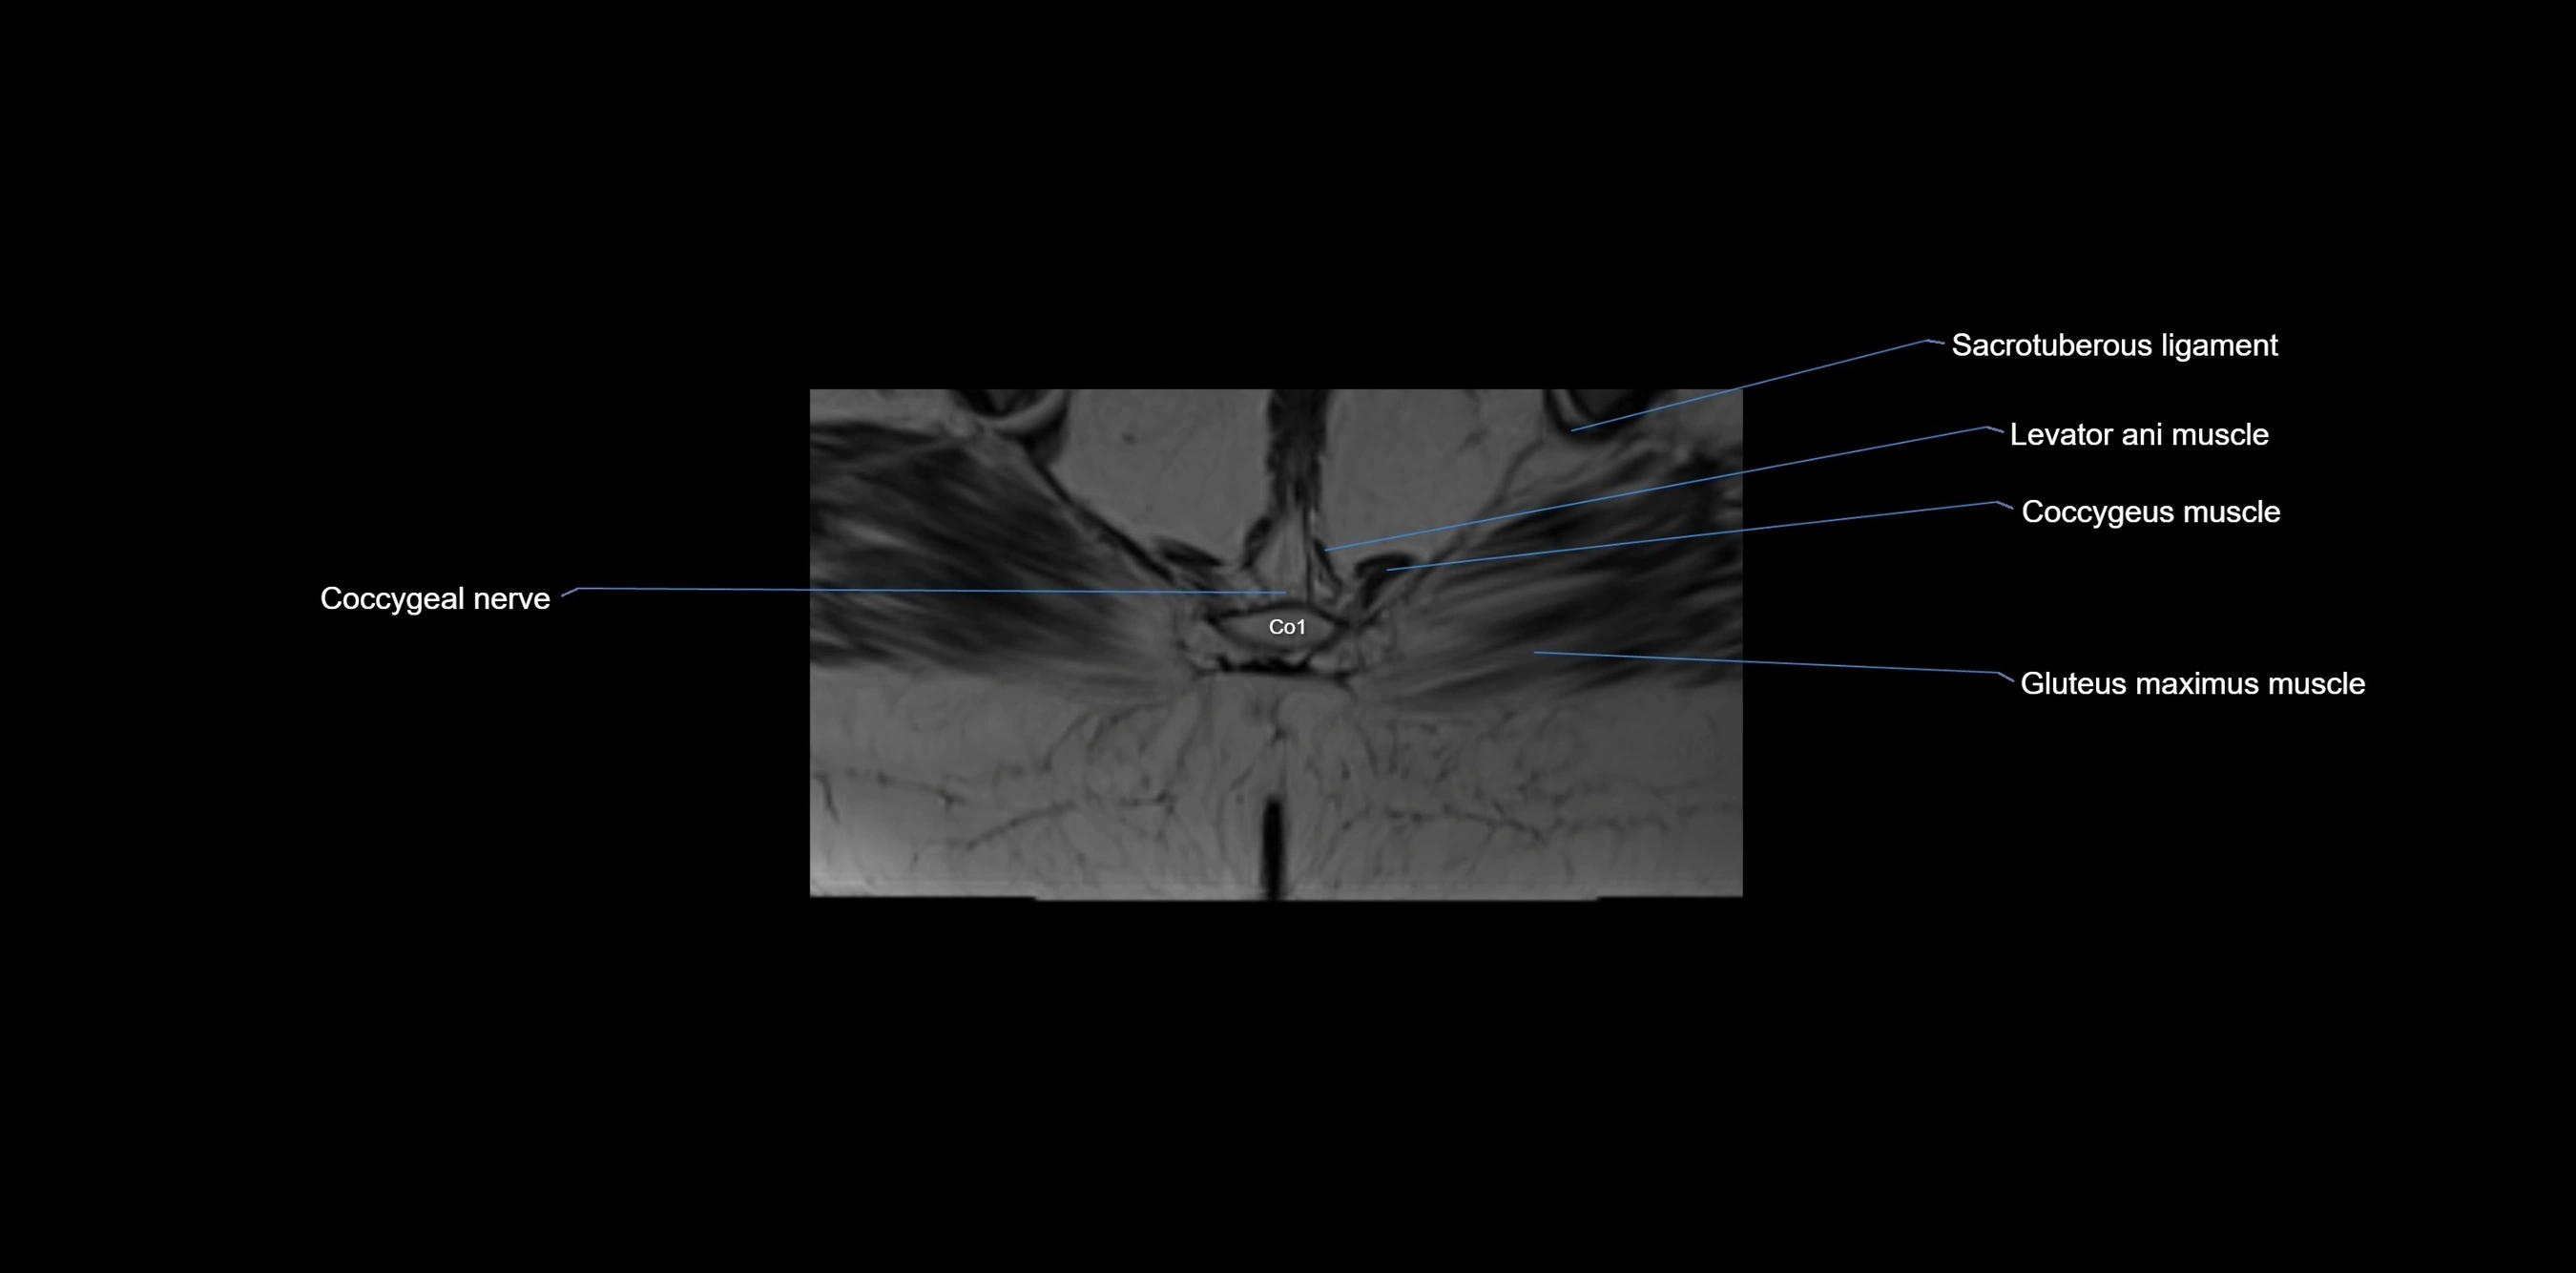

MRI Appearance

T1-weighted images:

• Cortical bone appears very low signal (dark); marrow shows intermediate signal

• Iliac fossa fat is bright against low-signal cortex

T2-weighted images:

• Cortical bone remains dark

• Marrow signal varies depending on fat content; edema or tumor shows hyperintensity

STIR:

• Suppresses fat, making bone marrow edema, fractures, or infiltrative lesions appear bright

• Excellent for trauma, sacroiliitis, and metastatic evaluation

T1 Fat-Saturated (Pre-contrast):

• Marrow: intermediate signal, fat suppressed

• Useful for detecting subtle marrow abnormalities adjacent to iliac cortex

T1 Fat-Saturated Post-Contrast (Gadolinium):

• Enhances vascularized structures, marrow pathology, tumors, and inflammatory changes

• Highlights soft tissue or bone invasion in pelvic neoplasms

MRI Non-Contrast 3D Imaging:

• Provides 3D morphology of iliac wing, crest, and articulations

• Used in preoperative planning for pelvic surgery and trauma reconstruction

MRI image

image